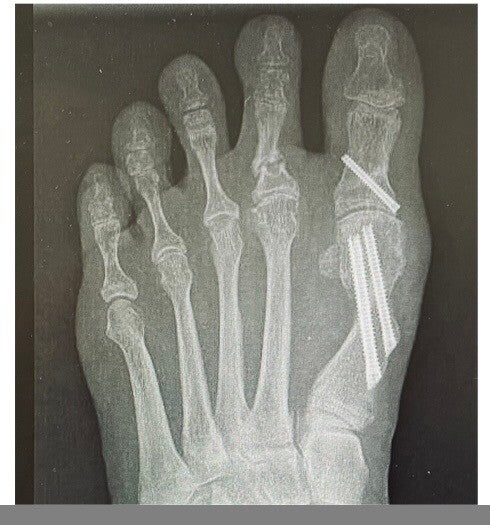

Er bestaan nog steeds misverstanden over hallux valgus-operaties, vaak gebaseerd op verouderde technieken waarbij alleen de knobbel werd verwijderd, zonder het scheefstaande voorvoetbeentje te corrigeren. Dit leidde vaak tot terugkeer van het probleem of zelfs verergering. Tegenwoordig maken chirurgen gebruik van moderne procedures die de gehele voorvoet corrigeren. De meest toegepaste methode is de Z-vormige doorwerking, waarbij de stukken worden verschoven zodat de teen weer recht komt te staan, en met twee schroeven worden vastgezet. Ook het gewricht wordt meteen in de juiste positie geplaatst.